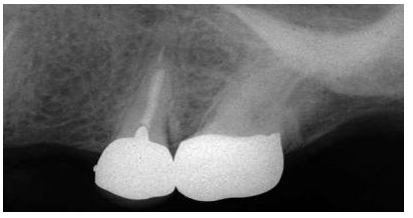

圖2:上頜第一前磨牙的根尖片,過(guò)長(zhǎng)的平行壁樁修復(fù),根尖部的牙膠量少于理想的5mm的根尖封閉

牙髓治療后的牙齒經(jīng)過(guò)樁道的預(yù)備,根尖部的牙膠是抵抗根尖周區(qū)域細(xì)菌傳播的屏障。許多研究結(jié)果都已經(jīng)證實(shí)當(dāng)根尖部的牙膠長(zhǎng)度僅僅是2mm到3mm時(shí),根管內(nèi)存在嚴(yán)重的滲漏;根尖部牙膠量為4mm到5mm能保證充足的根尖封閉。盡管多數(shù)研究結(jié)果都表明4mm的根尖牙膠量能提供充足的根尖封閉,但是樁道預(yù)備時(shí)要精確地達(dá)到4mm是非常困難的,根尖片拍攝角度的差異可能會(huì)導(dǎo)致根尖部保留的牙膠少于4mm。因此在根尖片上,根尖部牙膠5mm比4mm更為對(duì)根尖封閉安全有效。